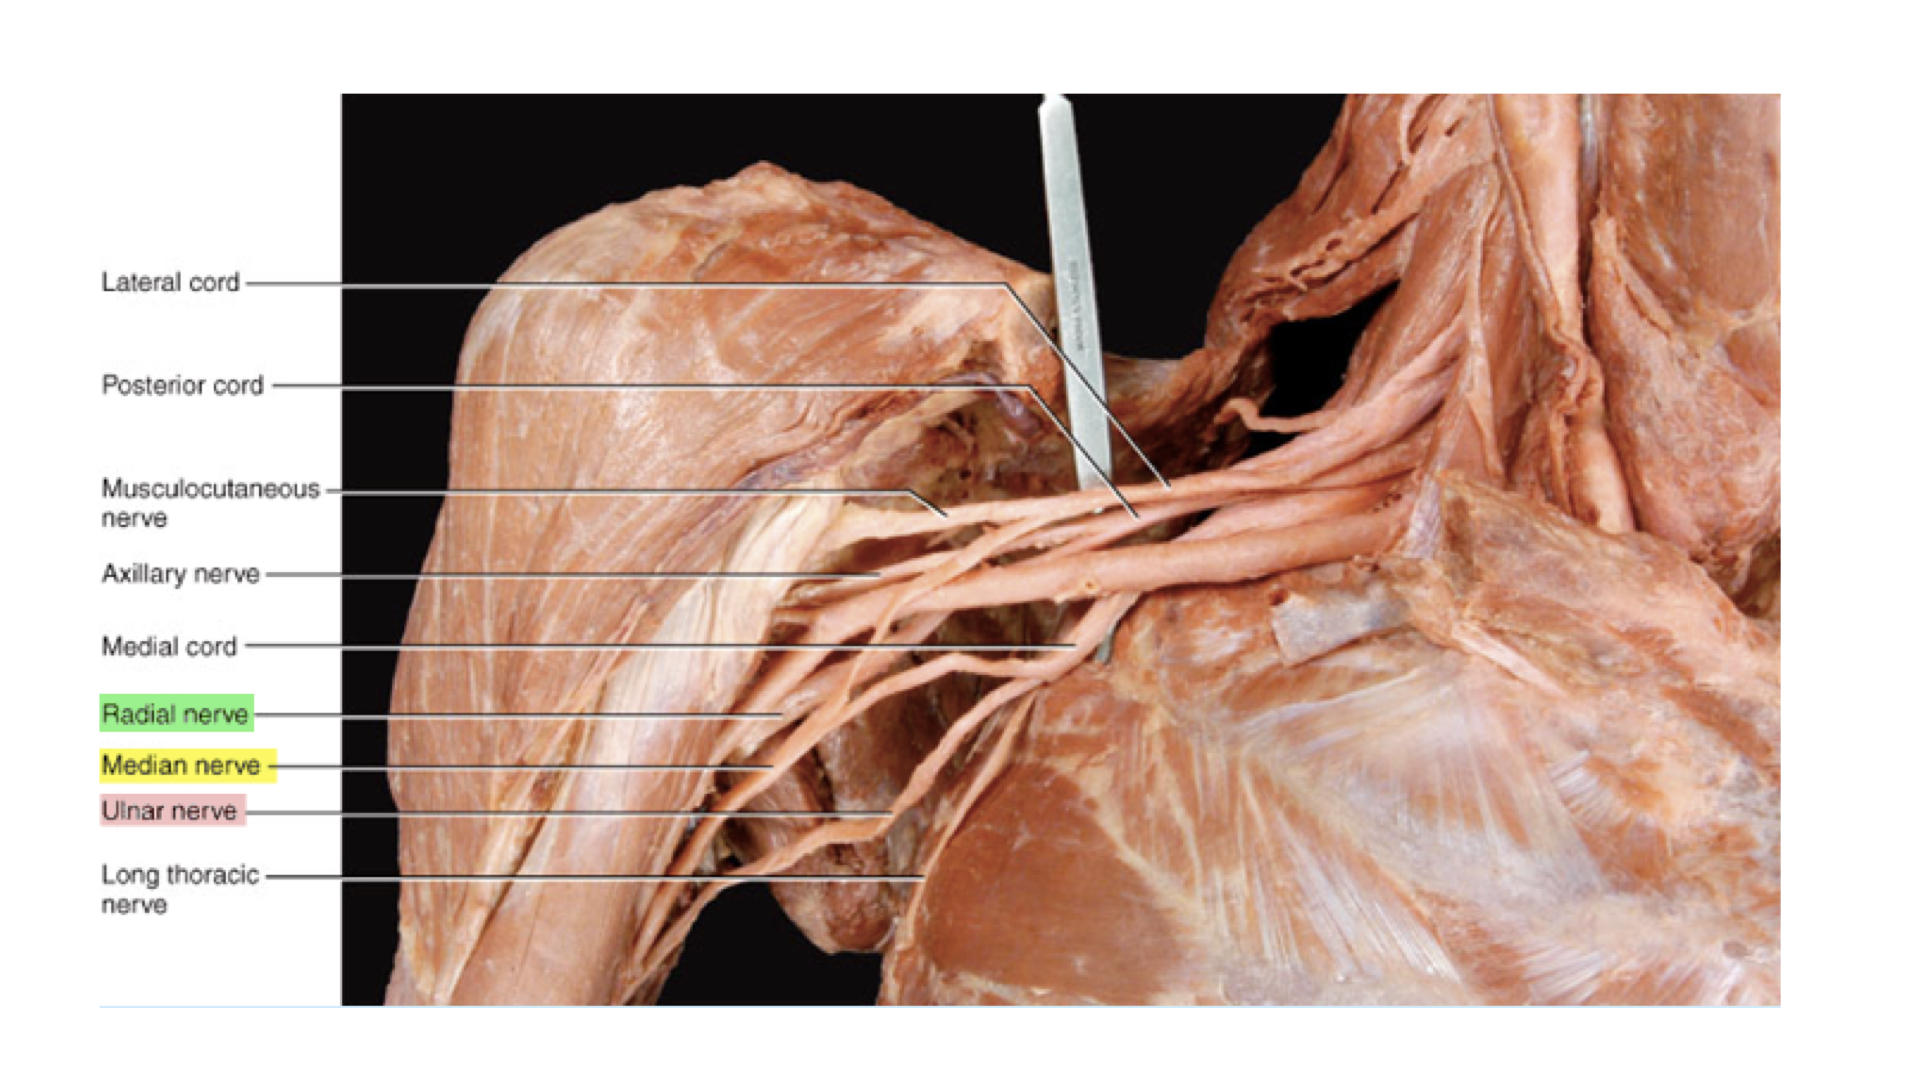

b. Brachial Plexus: The major nerves here are the radial, ulnar, and median nerves. The ulnar causes tingling down the forearm to the little finger when struck at the elbow--"crazy bone" response.

Brachial plexus with Radial, Ulnar, and Median Nerves Highlighted

Brachial plexus with Radial, Ulnar, and Median Nerves Highlighted